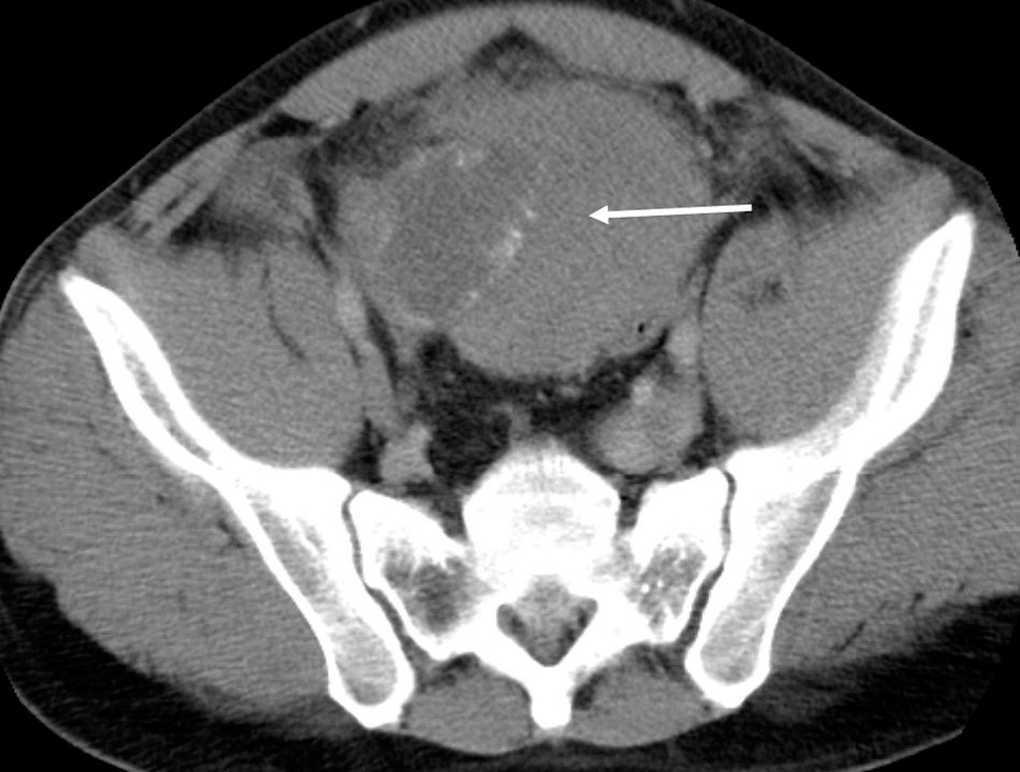

Varón de 33 años que acude a urgencias por dolor epigástrico de inicio súbito, constante e intenso. En la exploración física destacaba la presencia de una masa dolorosa en el hipogastrio, defensa abdominal con peritonismo generalizado y una criptorquidia izquierda. La tomografía computarizada (TC) mostró una masa de 10 cm en el hueco pélvico con gas en su interior, con alguna zona quística rodeada de tenues calcificaciones (fig. 1). En la laparotomía se objetivó líquido libre purulento y una voluminosa tumoración pélvica que englobaba parte del epiplón mayor, un asa de íleon, el apéndice cecal, parte del fondo vesical y el borde antimesentérico del sigma, el cual se econtraba infiltrado y perforado hacia la cavidad de la neoplasia. Se extirpó la tumoración en bloque con los órganos infiltrados (fig. 2). La continuidad intestinal se estableció mediante anastomosis intestinal y colónica, previo lavado intraoperatorio del colon. Del líquido abdominal se aislaron Escherichia coli y Clostridium perfringens. El postoperatorio transcurrió sin complicaciones. El informe anatomopatológico fue de seminoma de 10 cm que infiltraba el intestino delgado, el epiplón, el apéndice y el sigma.

Fig. 1.